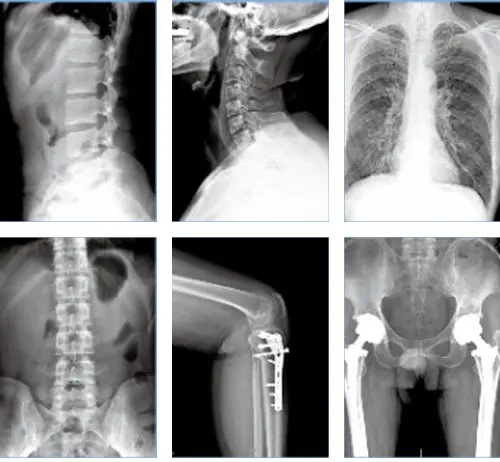

PLX8500C/D DRHigh Frequency Digital Radiography System● The high imaging output of 55kW and 65kW allows short-time radiography, virtually eliminating any motion burring.

| SHARP IMAGE SUPPORT YOUR ACCURATE DIAGNOSE55/65kW generator make us different, our generator assures the best image in every operating condition along with reduced patient dose and extend X-ray tube lifetime.

● Convenient image processing system and high definition medical display system provide efficient and accurate diagnosis.

Flat panel detector improvse your workflow, exam speed and comfort with efficiency.

A-si detector with CSI screen,excellent spatial resolution

Active area:17” x17”